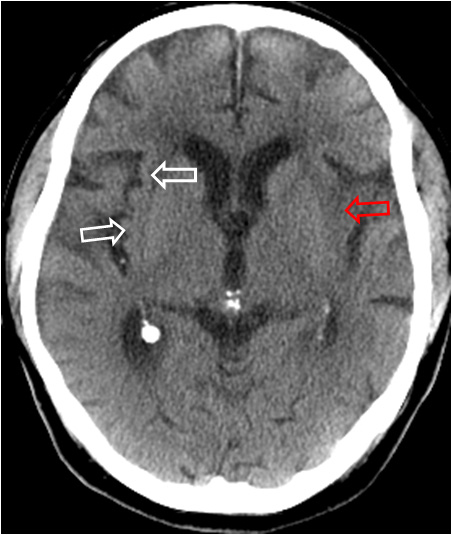

SIGNO DE LA PÉRDIDA DE LA CINTA INSULAR

Es otro de los signos precoces de infarto del territorio de la arteria cerebral media, que corresponde al oscurecimirnto de la sustancia gris en el margen de la corteza insular, con pérdida de la diferenciación entre la sustancia gris y la blanca. En la imagen vemos el signo en el lado izquierdo (flecha roja). A la derecha, las flechas blancas marcan la sustancia gris conservada de la corteza insular.

Este signo precoz es debido a la susceptibilidad de esta zona de corteza a la isquemia por oclusión de la arteria cerebral media, debido a la menor capacidad para suplir la vascularización a través de colaterales desde las arterias cerebrales anterior y posterior.